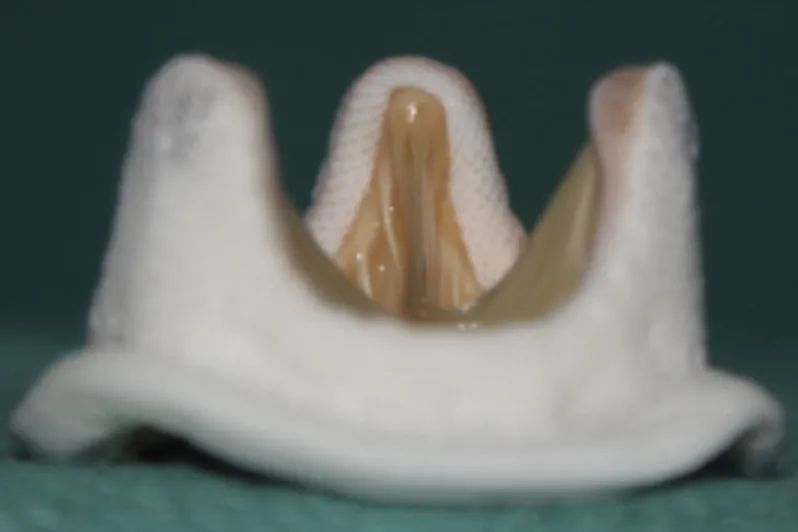

患者2007年植入HANCOCK 23号外科生物瓣,生物瓣衰败后内径为21.8 mm,术前超声评估除瓣中明显反流外,右无窦区域明显瓣周漏,综合评估,决定行血管塞封堵瓣周漏联合TAVR行瓣中瓣术式。

根据造影情况决定选择VenusA 23号瓣膜